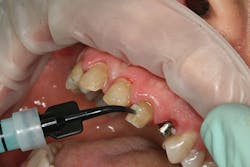

At the beginning of the impression appointment, the provisionals were approved for fit and esthetics with a particular focus on emergence profile of the implant provisionals. Profound anesthesia was achieved and the bisacrylic provisionals were removed. The preparations were cleaned with chlorhexidine (Consepsis, Ultradent) and the abutments were once again removed (figure 10). The open-tray impression copings were then tried in, their seat confirmed radiographically, and then modified into custom impression copings with flowable composite (figures 11-14). Once appropriate tissue support was confirmed, the open-tray master impression was made with a heavy and light body wash technique using vinyl polysiloxane impression material (Honigum, DMG America) (figure 15). Following the master records, the provisional abutments and bisacrylic provisionals were replaced until the seat appointment.